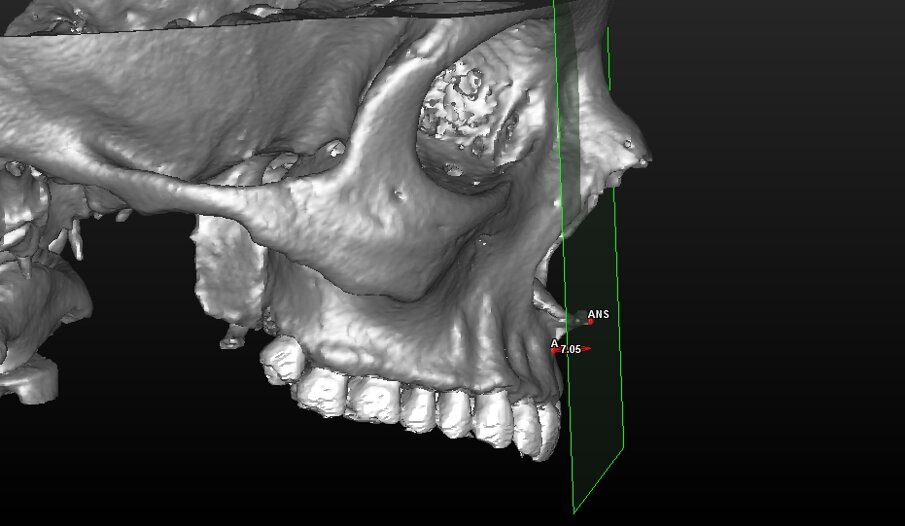

In base agli studi eseguiti da Enlow sulla crescita delle strutture craniche ci sono dei processi di apposizione e riassorbimento a carico della zona maxillare anteriore ma che non interessano l’apice della spina nasale anteriore (Fig. 12) (Fig. 13). Solo 2 casi su 50 totali (uomini + donne) hanno presentato una discrepanza tra la posizione reale e quella ipotizzata > 1mm (Grafici 1, 2). Nelle donne non ci sono casi che presentano una discrepanza della misura UIm-ATP > 1 mm ma 8 casi che si presentano fuori dal range di idealità < 1 mm (32%). Sul totale del campione analizzato circa il 76% si trova all’interno dell’intervallo di normalità e solo 2 casi si trovano invece fuori dal range <1 mm (Grafico 3).

Fig. 12_Rappresentazione grafica della modalità di crescita dell’osso maxillare con le varie superfici di riassorbimento e di apposizione che non toccano l’apice della spina nasale anteriore che non subisce modificazioni. Il punto A (subspinale) è considerato come punto di inversione tra apposizione-riassorbimento.

Fig. 13_Ricostruzione 3D di un soggetto che presenta il margine incisale degli incisivi superiori (punto UIm) a livello della spina nasale anteriore e contestualmente un angolo naso-labiale corretto.